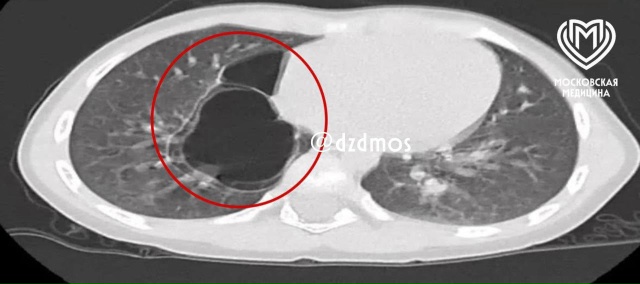

В Москве врачи спасли жизнь школьнице, у которой начались проблемы с дыханием после попадания шелухи от семечки в легкое. После операции ее отправили на дополнительное обследование. Часть скорлупы семечки глубоко впаялась в третий субсегмент правого легкого, из-за чего у пациентки образовался бронхоэктаз, то есть плохо функционировали из-за скопления гноя бронхи.